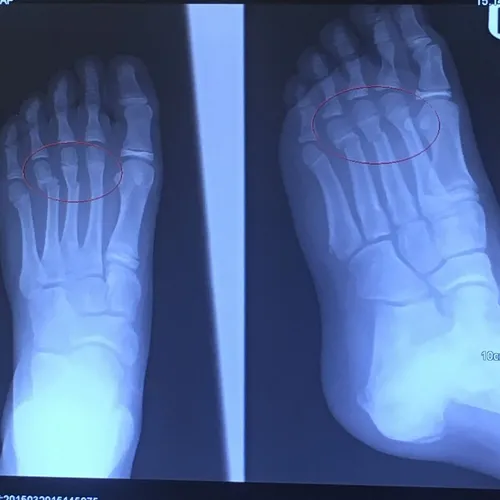

Pediatric Displaced 5th Met Distal shaft/neck fracture

Preop Pics of the displaced fracture prior to Percutaneous Fixation and Reduction

We percutaneously put a pin across the fracture after closed reduction for 12-16 weeks. The last picture is a final after the fracture is healed and the pin is removed.